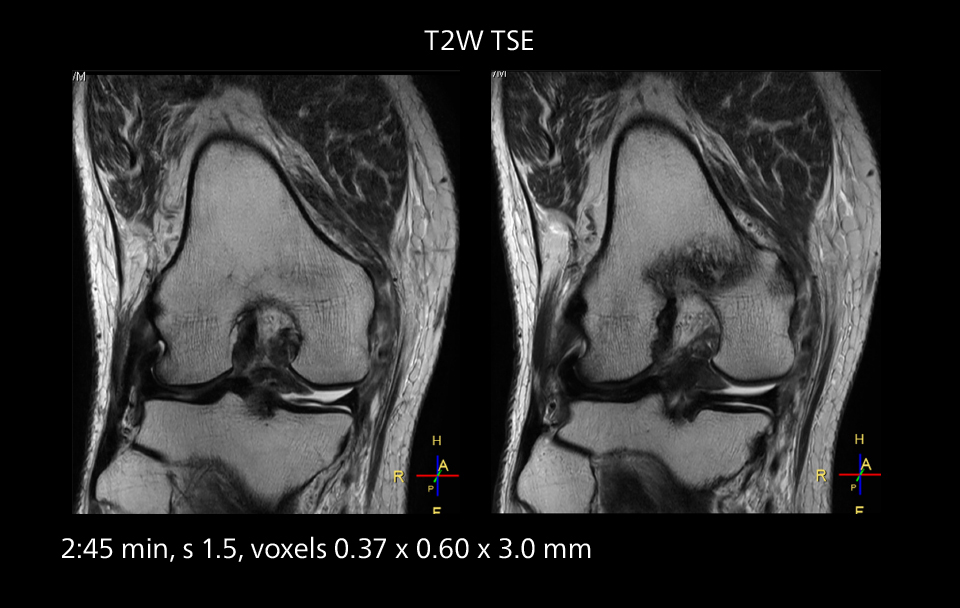

An example of increased imaging speed is in knee studies. “There is a definite scan time reduction for T2* mFFE and proton density TSE – both of these sequences benefit from much shorter repetition times,” he reports.

MRI of the knee

Images showing a posterior cruciate ligament (PCL) tear, a detached medial collateral ligament (MCL) on the tibial side and an intact anterior cruciate ligament (ACL). SmartPath to Elition X helped reduce scan time compared to previous imaging while maintaining resolution.

Overall, imaging time per sequence has been reduced since the Elition X upgrade. This can help reduce the risk of patient movement and the need for rescans.